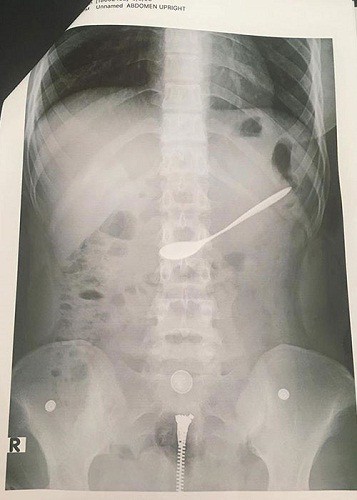

Hình ảnh chiếc thìa trong bụng nữ bệnh nhân. Ảnh: Người Đưa Tin. |

Trong lúc uống cà phê, cô gái trẻ 20 tuổi vô tình nuốt luôn cả chiếc thìa cà phê bằng sắt vào trong bụng.

Cụ thể, trong lúc uống cà phê, cô gái 20 tuổi, trú tại TP.Vinh tỉnh Nghệ An đã vô ý nuốt thìa cà phê vào trong bụng. Ngay sau đó, mọi người đã nhanh chóng đưa cô gái tới bệnh viện Đa khoa TP.Vinh để cấp cứu.

Tại bệnh viện, nữ bệnh nhân được chuyển đến phòng Nội soi Tiêu hóa. Sau khi làm các thủ tục cần thiết, các bác sĩ của bệnh viện đã tiến hành gắp thìa cà phê ra khỏi người bệnh nhân.

"Sau khi tiến hành nội soi, các bác sĩ của bệnh viện đã gắp chiếc thìa ra khỏi người bệnh nhân"- ông Nguyễn Hồng Trường, Giám đốc Bệnh viện Đa khoa TP Vinh, tỉnh Nghệ An cho biết.